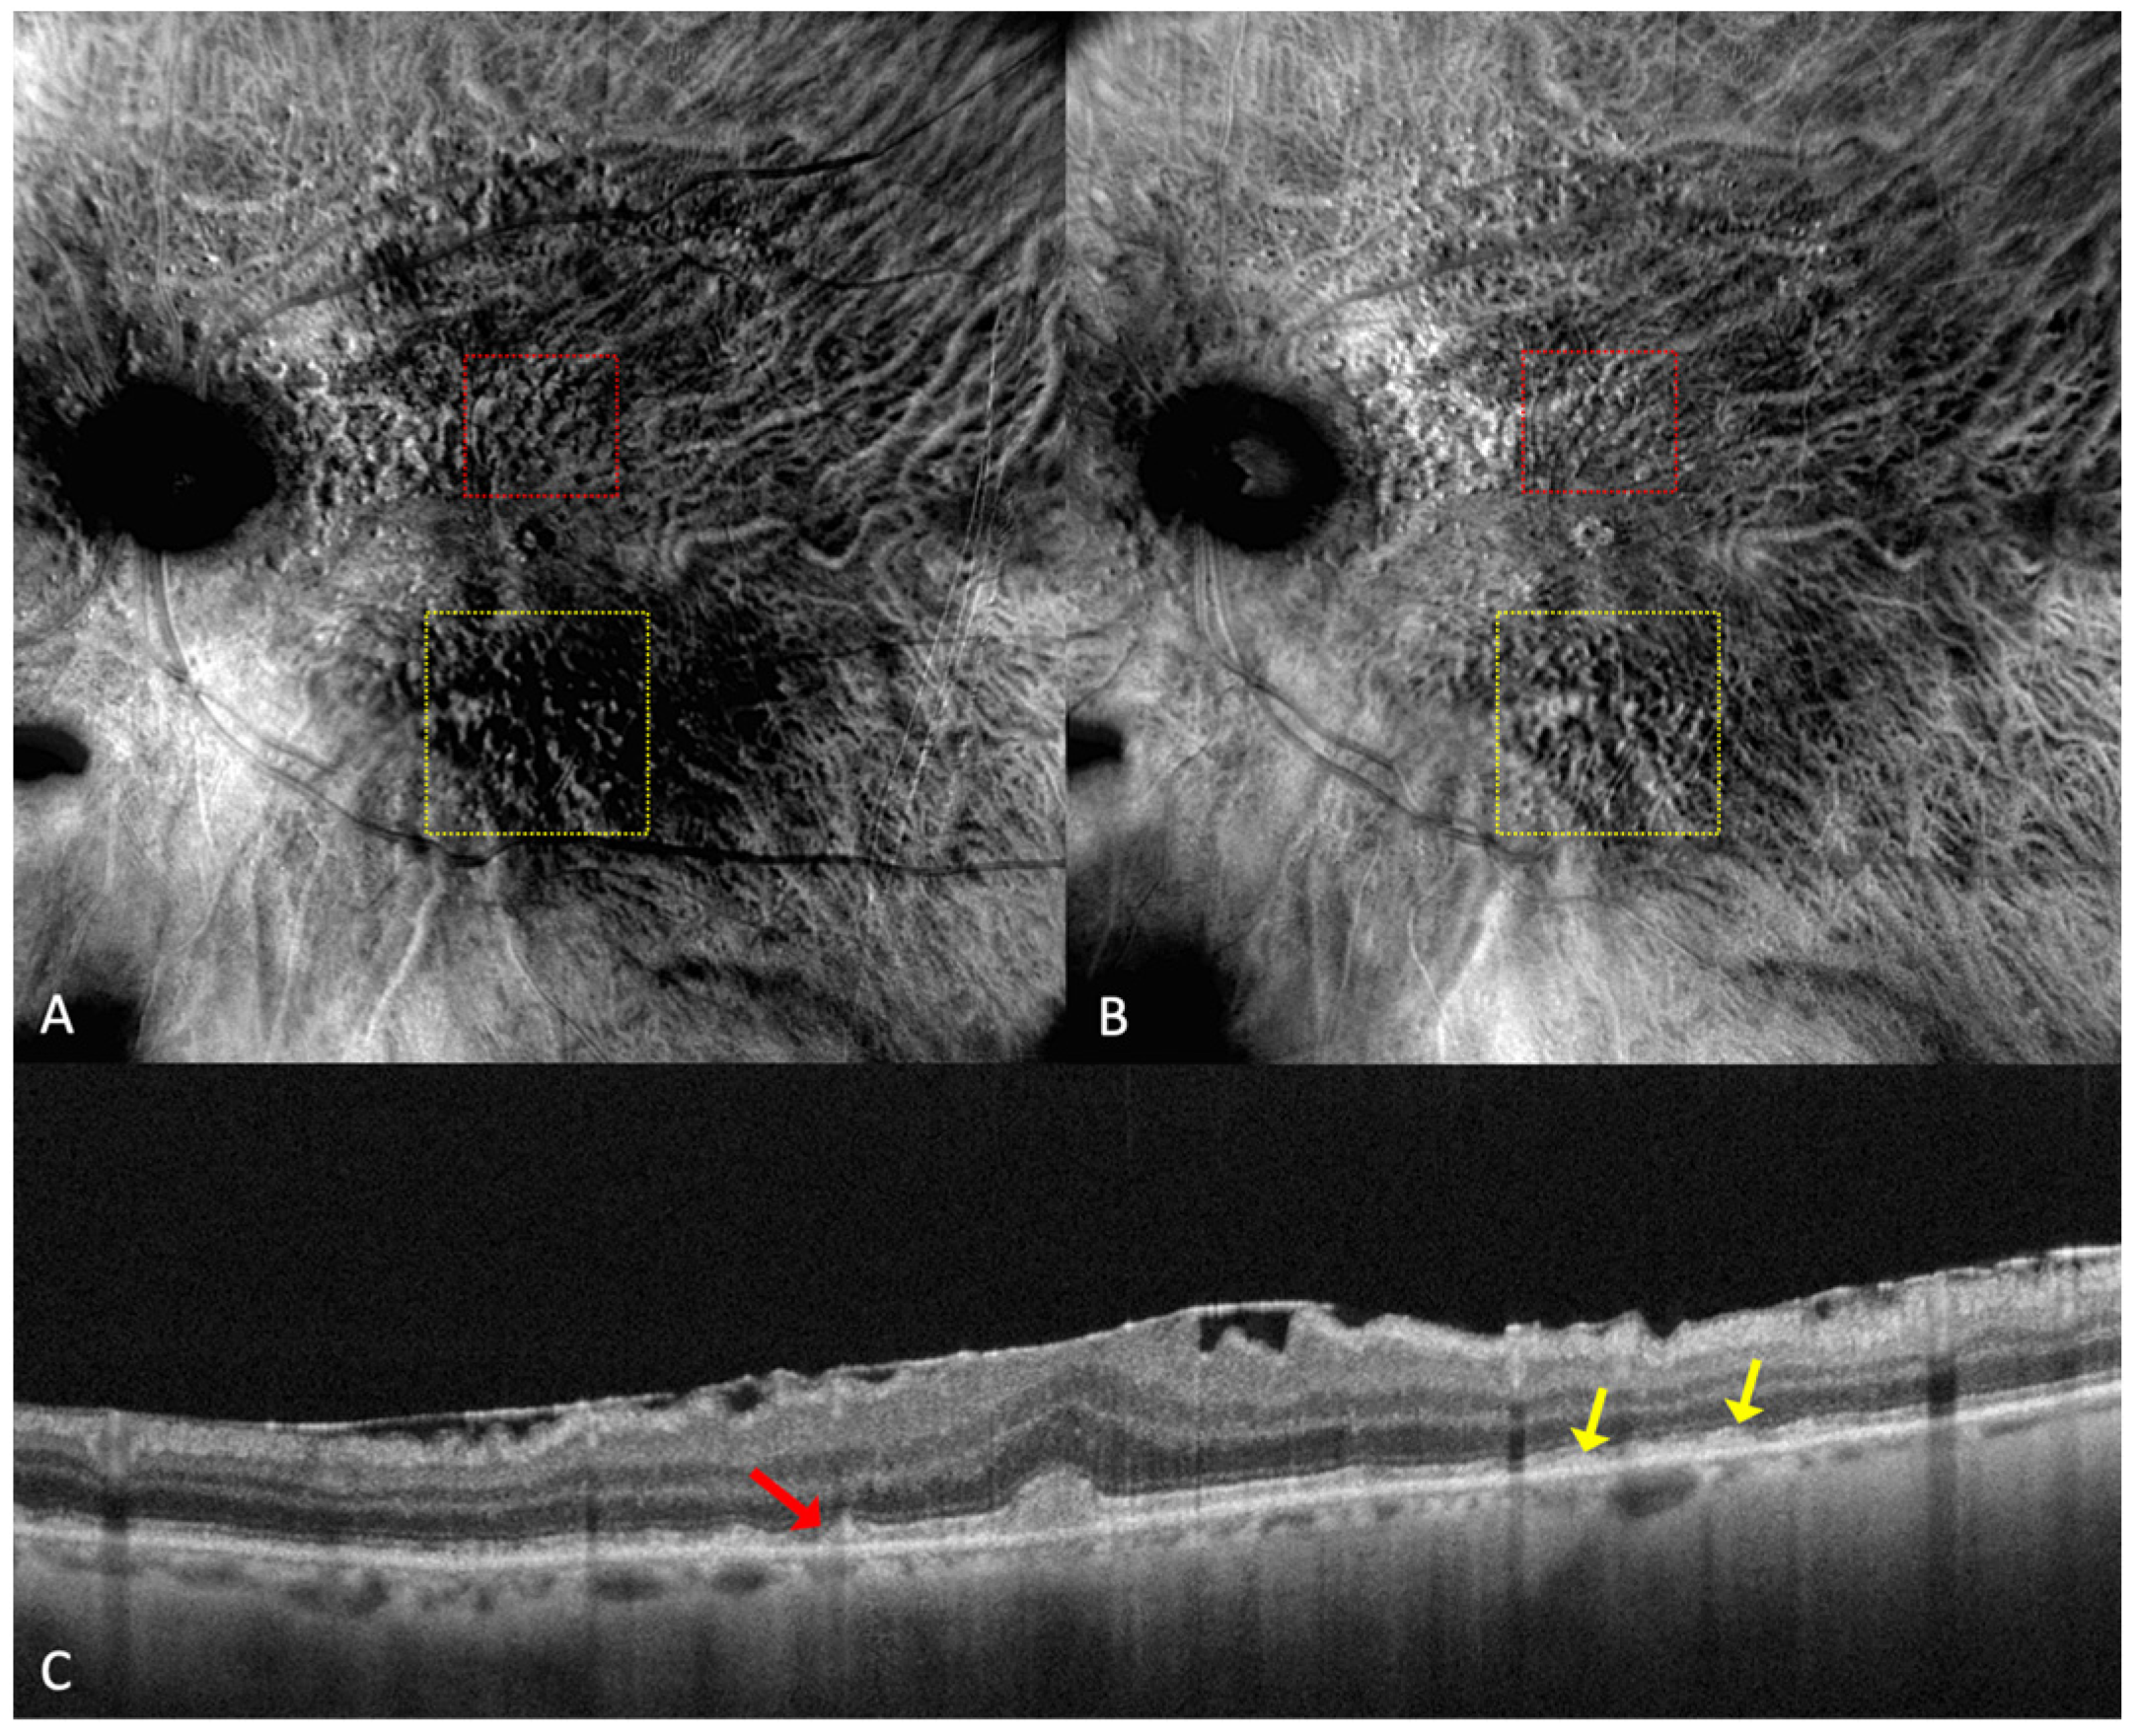

Figure 5.

Drusen and dot subretinal drusenoid deposits (SDD) in a patient with co-existent angioid streaks: (A) cSLO showing multiple drusen and SDDs, with peripapillary radiating irregular lines. (B) In green FAF, temporal to the fovea, drusen are seen as hypo- and hyper-autofluorescent round lesions. (C) In retromode deviated right, elevated lesions can be seen, and in (D) retromode deviated left, small, depressed lesions are detected. (E) En face OCT of (F) SD-OCT shows multiple small, medium, large drusen and also dot SDD (red arrow).

Parravano et al. conducted a study on reticular pseudodrusen imaging. Considering the characteristics of the lesions by their aspect on retromode images, the deposits were classified as round, bended, or interlacing [31].

Cozzi et al. investigated the accuracy of different retinal-imaging modalities in AMD patients. The study found that dot SDDs are hard to detect with retromode because of their high resemblance to small drusen, so the method’s accuracy is reduced in both DR (64.6% sensitivity; 85.7% specificity) and DL (76.6% sensitivity; 83.3% specificity), in comparison to other investigations [24]. The authors also specified that the DR or DL modes might not be able to detect ribbon SDDs due to their small size [24].

Dot SDDs in the retromode DR mode appear as pseudo3D round, hyporeflective lesions, and in the DL mode, they appear to have a target aspect—a hyperreflective halo surrounding a hyporeflective center. Ribbon SDDs are hardly detectable in the retromode illumination DR, and in the DL mode, they have a “reticular pattern” [24].